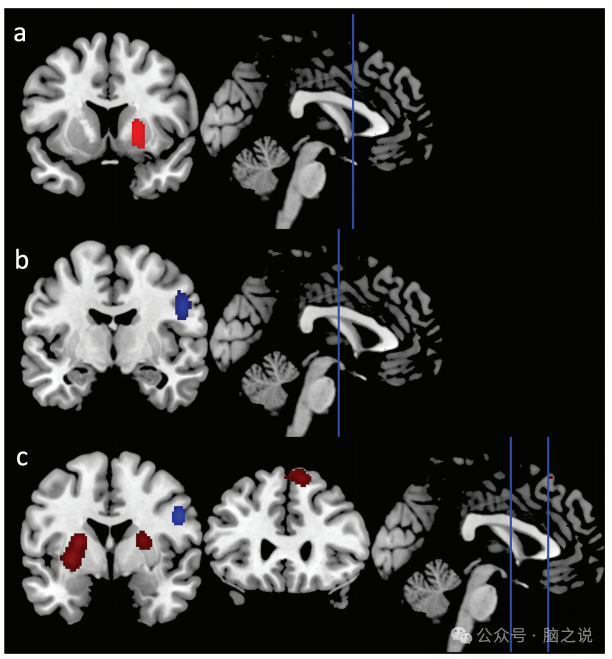

AIFF / fAIFF。与对照组相比,FEP组右侧纹状体的AIFF/fAIFF值较高[峰坐标(x,y,z) = 22,12,2]。

ReHo。对7项研究的探索性分析显示,与健康对照组相比,FEP患者的ReHo在右侧中央前回和IFG[峰坐标(x,y,z) = 50, - 4,30]、右侧缘上回[峰坐标(x,y,z) = 33, - 39,42]和左侧中央前回[峰坐标(x,y,z) = - 14, - 24,72]显著降低。

所有的测量。我们发现与对照组相比,FEP的AIFF/ fAIFF和ReHo在右侧纹状体[峰坐标(x,y,z) = 18,14, - 2]、左侧纹状体[峰坐标(x,y,z) = - 18,12, - 2]和双侧SFG/MFG[峰坐标(x,y,z) = 12,26,58]显著增加。此外,我们观察到右侧中央前回和IFG的AIFF/fAIFF和ReHo降低[峰值坐标(x,y,z) = 50, - 4,30](图4,补充表S.4-S.6)。

图4 与健康对照组比较,drug-naïve FEP的CBMA值有内在活性改变。